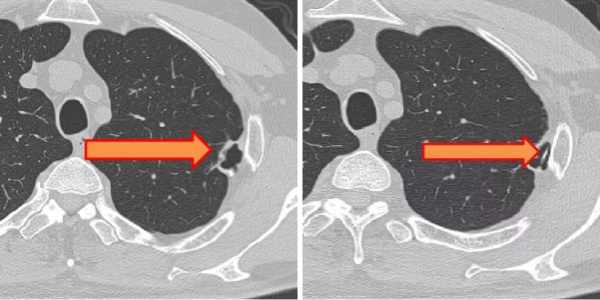

接诊后,崔健带领胸外科医疗团队为其进行了系统检查与全面评估。影像学检查发现患者左肺上叶存在异常阴影(术前影像图1、2)。团队结合临床经验初步判断并非普通肺部病变。经过与患者及家属充分沟通并完善术前准备,团队决定为王先生实施手术探查与治疗。

图1箭头处为肺部阴影;图2箭头处为肺部阴影内异常密度影